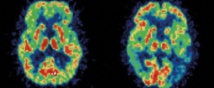

Densité importante de plaques bêta-amyloïdes (l’accumulation de plaques est une lésion caractéristique de la maladie) dans le cerveau, mise en évidence par imagerie TEP.